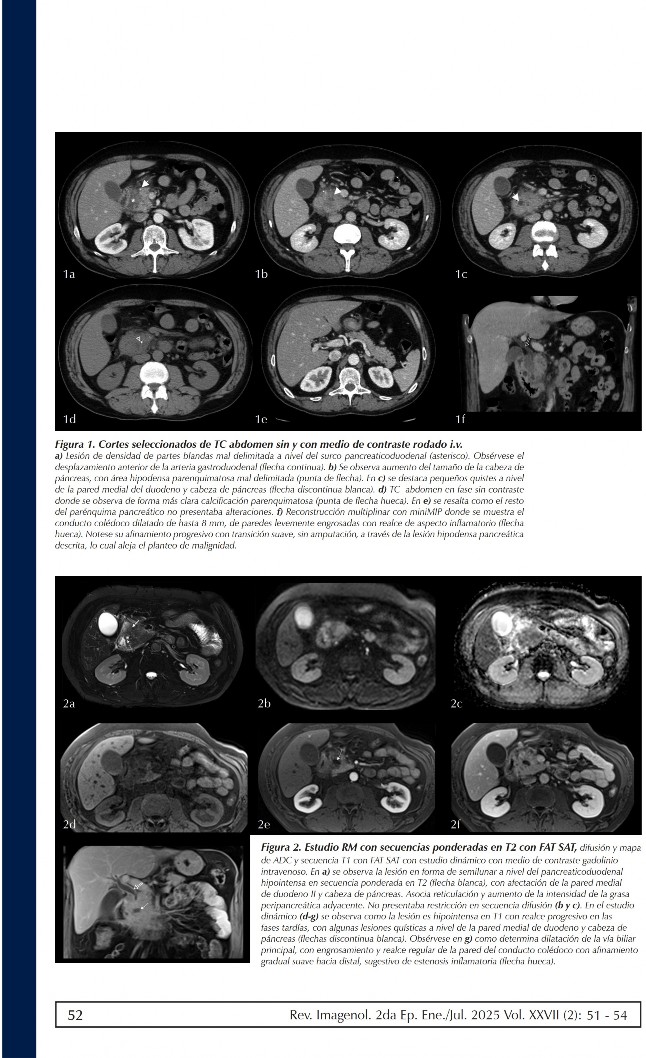

image